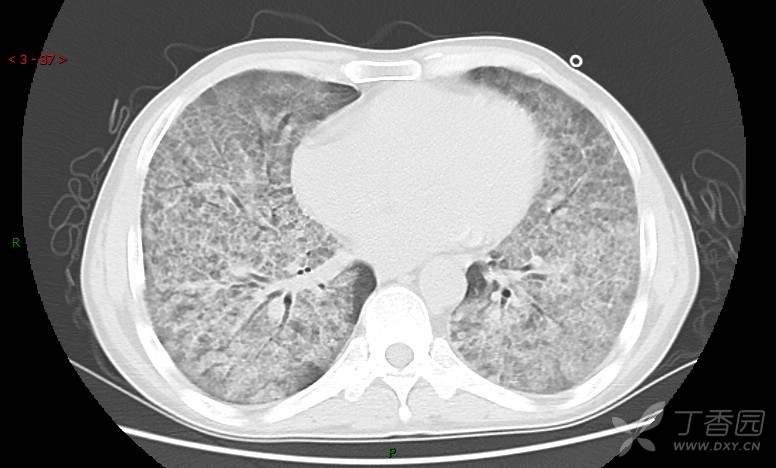

地图+铺路石征=PAP?那升高的CEA怎么说(病例3连发,附其他2例链接)

血清肿瘤相关抗原116.22U/ml↑(0--95);

癌胚抗原 61.96 ng/mL ↑ 0--5

神经特异性烯醇化酶 33.12 ng/ml ↑ 0--16.3

细胞角蛋白19片段测定 40.23 ng/ml ↑ ≤3.3